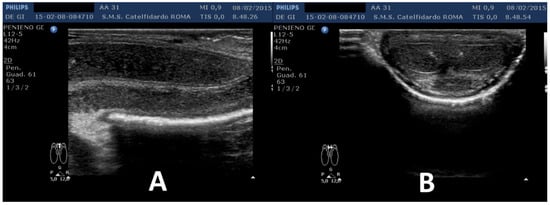

| 2 | 52 years | Dupuytren’s disease, Ledderhose disease, congenital dorsal penile curvature (5 degrees). | Middle third + distal third | (A) First plaque: 13.4 × 9.15 × 2.83 mm volume = 182 mm3. Second plaque: 14.8 × 8.43 × 3.87 mm. Total volume = 252 mm3 (B) No plaque detected | (A) 20-degree dorsal penile curvature + 20-degree left penile curvature (B) 5-degree dorsal penile curvature. Previous condition = congenital dorsal penile curvature (5 degrees) | VAS score = 0 | 26 > 27 | 51 months | Orally: propolis 600 mg + bilberry 160 mg + silymarin 400 mg + ginkgo biloba 250 mg + L-carnitine 1000 mg + coenzyme Q10 100 mg + Boswellia 200 mg + vitamin E 30 mg/daily for 51 months + topically: diclofenac gel 4%/2× daily for 51 months + periplaque penile injections: pentoxifylline 100 mg (30 G needle) every 2 weeks for 6 months, and then 1 penile injection every month for 12 months, and 1 penile injection every 2 months for 24 months (42 total injections) |